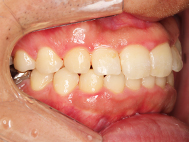

After

| 症状 | 上顎前歯部叢生 |

上の前歯がハの字隣の歯が引っ込んでいる

前歯のガタガタが気になるとの事で来院されました。

装着が目立ちたくないとの事でアライナ-での矯正を希望されました、歯の間を削り少し歯の幅をスリムにして綺麗なアーチに並びました。